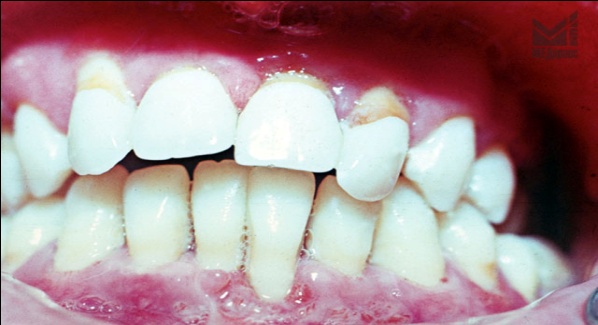

| Рис. 2. Равномерный остеолизис альвеолярного отростка в области всех зубов с четко выраженной сохранностью тела и ветвей нижней челюсти. |